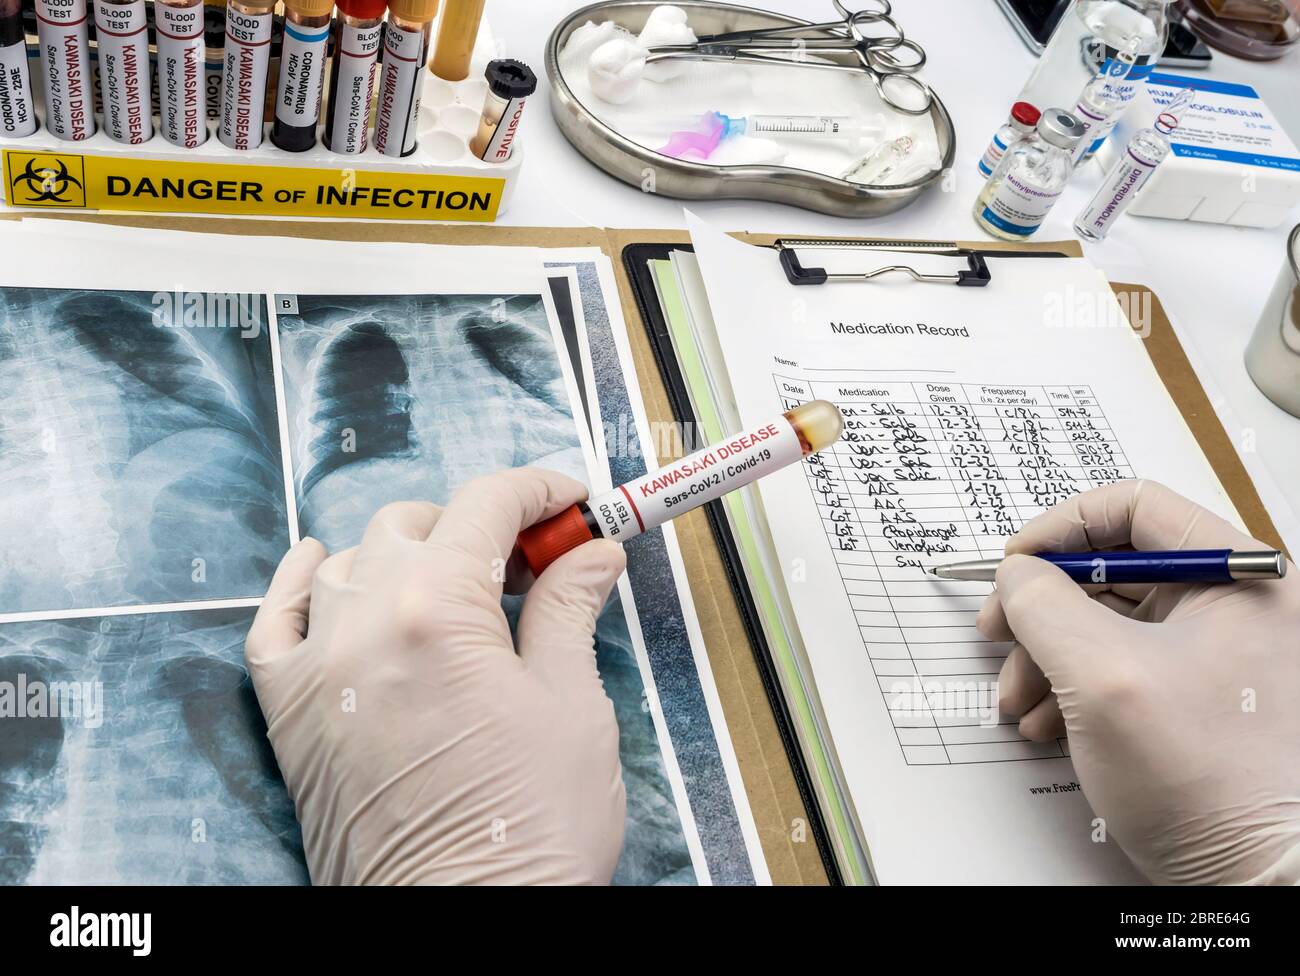

RF2BRE64G–Le médecin détecte les résultats dans la pulmonaire d'un enfant affecté par la maladie de Kawasaki avec plusieurs échantillons de sang dans un hôpital, image conceptuelle